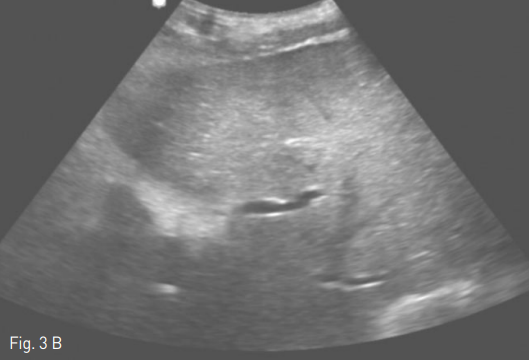

Fig 3B

Oblique axial plane was reconstructed (A) before performing procedure to facilitate sonographic guidance to puncture the left portal vein and left hepatic vein (B).